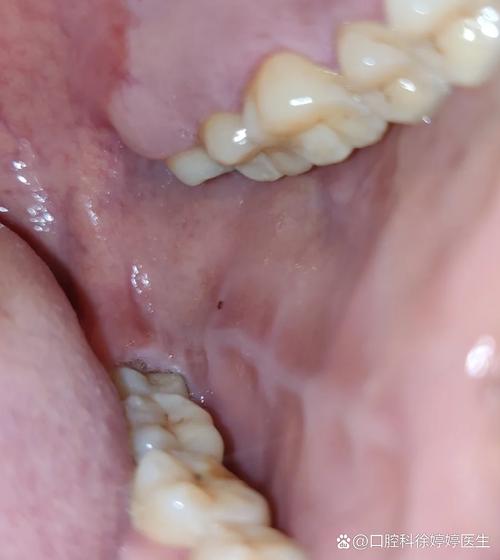

口腔咬合线发白突起是何问题?

“口腔咬合线发白突起”的示意图文字描述 您可以对照镜子,观察自己口腔内上下牙齿接触的区域(即咬合线),看看是哪种情况最符合。(图片来源网络,侵删) 最常见的可能性 —— 创伤性溃疡(咬伤) 这是最常见的原因,通常是由于不小心咬到了自己的口腔内壁(颊黏膜)造成的。 外观描述: 颜色: 表面呈白色或淡黄...